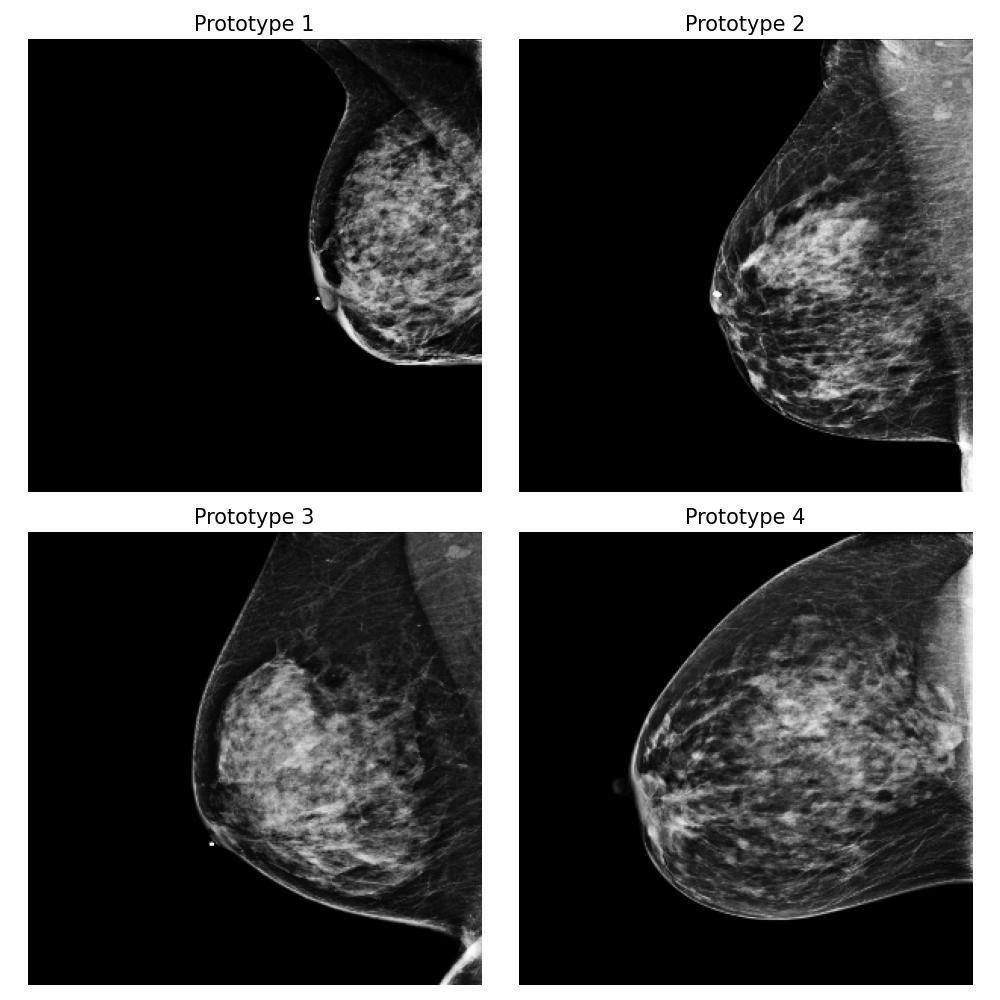

3.5.4 Case Study 2: Medical Image Data - Mammography Patient Population Dataset

In this case study, we assess the effectiveness of our proposed method in a realistic application, focusing on identifying differences between mammograms from two distinct patient populations. Specifically, we simulate a real-world scenario where users deploy models to analyze mammograms of women with varying tissue density distributions — a challenge commonly encountered when comparing premenopausal and postmenopausal patients or younger and older individuals. Premenopausal or younger patients often exhibit denser breast tissue, whereas postmenopausal or older patients often present with less dense tissue (Kim et al., 2020). This dataset evaluation step is crucial before deploying a clinical breast cancer risk detection model across different patient populations.

Dataset and

We use the publicly available EMBED dataset (Jeong et al., 2023). To simulate premenopausal and postmenopausal patient populations, we construct two datasets, and , by randomly sub-sampling from EMBED. Dataset comprises 27,224 mammograms from 8,456 patients with dense breast tissue (density category three in EMBED) and 21,675 mammograms from 7,841 patients in density category two. Dataset includes 27,224 mammograms from 2,715 patients with less dense tissue (density category one) and 21,675 mammograms from 7,797 patients in density category two (medium density). All mammograms were preprocessed to remove clinical markers and aligned such that the breast tissue faces left.

Forming the explanation

For this task, we implemented the “Prototype-summarization-based explanations” described in Section 3.5. We trained a binary vs classifier using the VGG19 feature extractor as backbone and learn four prototypes for each dataset. 97798 mammograms were used for training, and 24450 mammograms were used for testing.

Result

By examining the summarization prototypes shown in Figure 22, we identified tissue density as the primary difference between and . In mammograms, brighter areas correspond to denser tissue. Additionally, we observed that less dense tissue is often associated with larger tissue size. Without our proposed method, human users would need to manually analyze the dataset, which is a labor-intensive and time-consuming task, to reach the same conclusions.

Robustness of the explanation

To examine the robustness of our explanation result, we repeat the explanation algorithm approach on bootstrapped versions of and . Five bootstrapped datasets were constructed by resampling by patients with replacement. As shown in Figure 35 in Appendix Section B.5, we reach the same conclusion for all the bootstrapped datasets.

Coverage evaluation

We again evaluate the coverage quality of the learned set of prototypes using the AUCC score. The coverage curve is shown in Figure 24. We also display the learned latent space for and in Figure 24 and the two datasets and the prototypes are well separated even though they contain overlapping mammograms with density category two (i.e. medium density breasts).